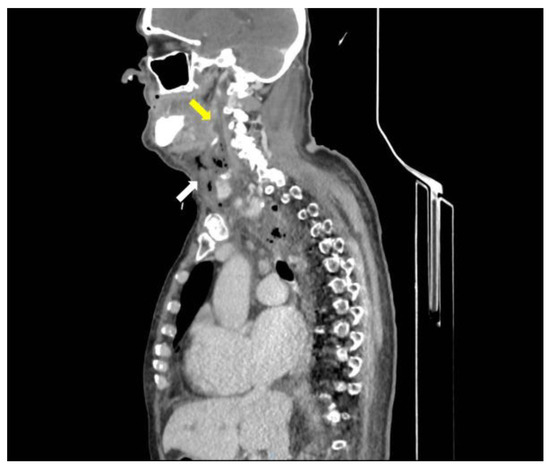

A CT scan of the head, neck, and chest with intravenous contrast, revealed a retrotonsillar fluid collection, with a maximum diameter of 10 cm, extended anteriorly to the right lobe of the thyroid gland (Figure 1). Air bubbles and minimal fluid were present from the right submandibular area to the lower mediastinum between the spine, the descending thoracic aorta, and the trachea (Figure 2).

Figure 1.

CT scan of head, neck, and chest with intravenous contrast material, shows a retropharyngeal collection (yellow arrow) and submandibular air bubbles (white arrow).